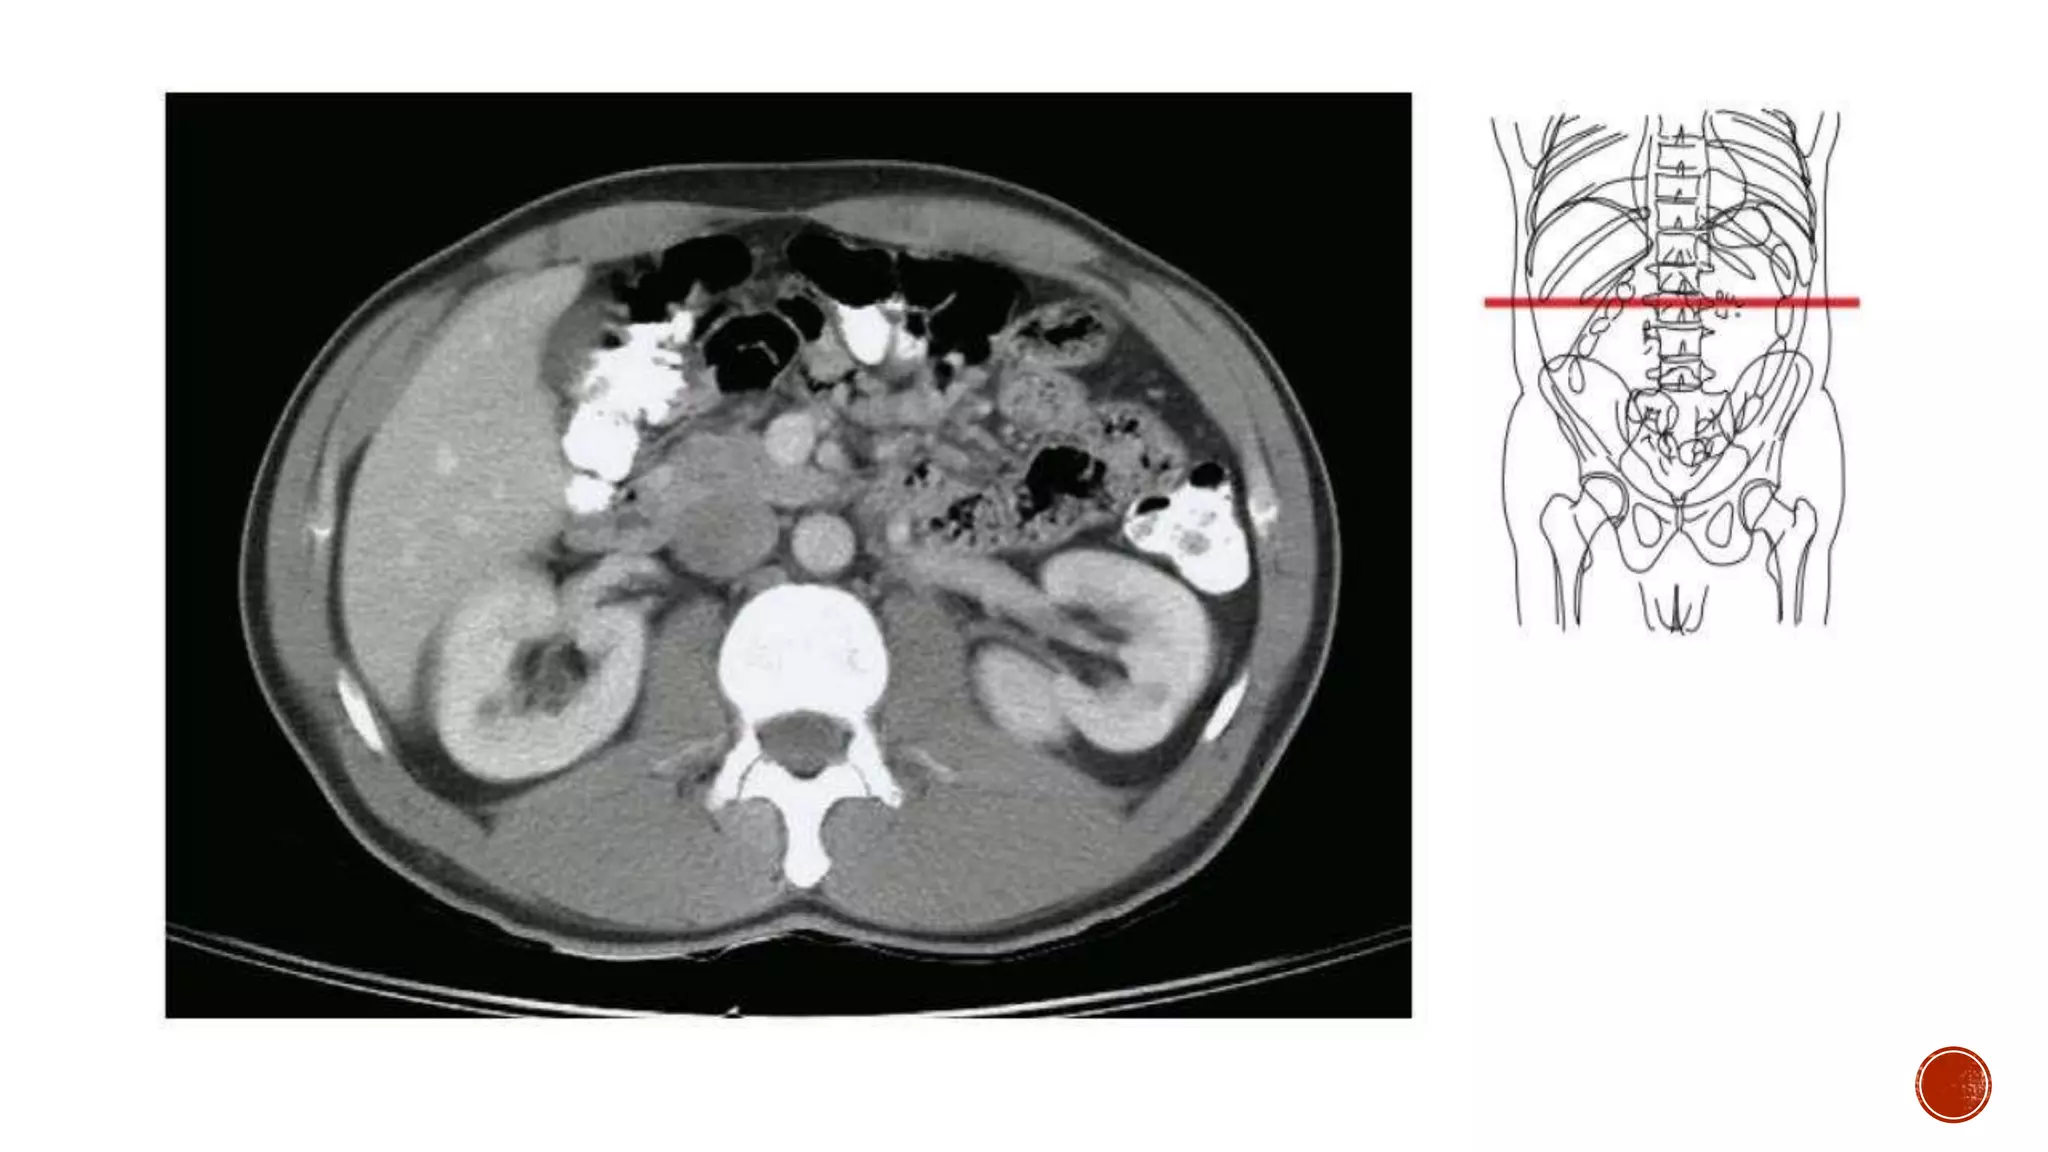

The document describes the anatomy of the abdomen and pelvis region of the human body. It lists over 40 structures and their locations, including major organs like the liver, kidneys, intestines, blood vessels and muscles of the abdominal wall and pelvis. The structures are grouped into sections focusing on different anatomical areas like the abdomen, retroperitoneum, pelvis and gluteal region.